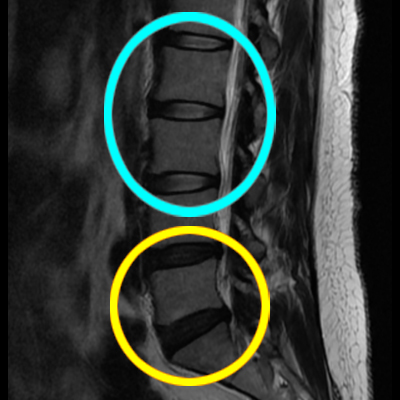

심각성을 인지하고 병원에서 개인실비로 mri이를 찍었는데

디스크는 터져서 흐른상태입니다.

제가 계속 아팠던게 교통사고 휴유증이 아닌

허리디스크 터짐이였습니다.

차에 탄 상태로 정상인 디스크가 터지려면

허리가 접혀야됩니다.

이미진행중인 디스크가

사고로 인해 터질수는 있습니다.